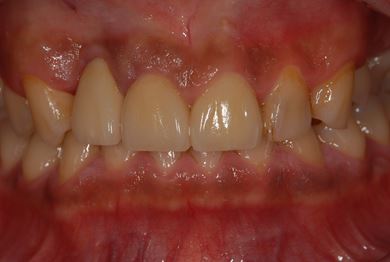

| 性別/年齢 | 男性 / 36歳 | ||||||||||||||||||||||||||||||||

| 主訴 | 歯が折れているので、インプラントにしたい。 | ||||||||||||||||||||||||||||||||

| 治療方針 | 抜歯と同時にインプラント埋入を行い、治療期間を短縮する。 | ||||||||||||||||||||||||||||||||

| 治療内容 | インプラント2本(抜歯即日インプラント治療)、ジルコニアフレームオールセラミッククラウン1本、オールセラミッククラウン2本(セラミック用土台2本)、メタルボンドセラミッククラウン1本 | ||||||||||||||||||||||||||||||||